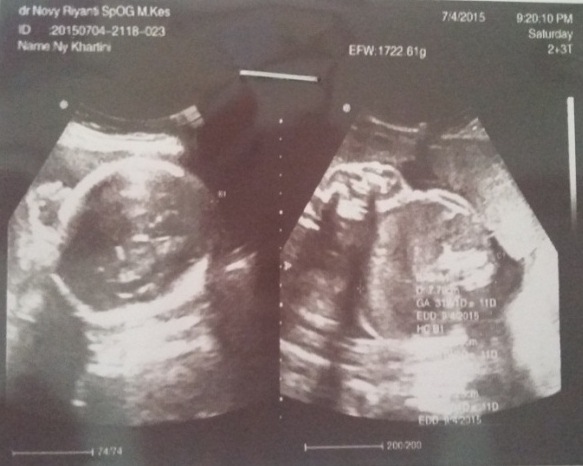

ASUHAN KEBIDANAN PATOLOGI PADA PERSALINAN DENGAN KASUS DISTOSIA BAHU Diagnosa: contoh askeb patologi kebidanan kasus akseptor pada KB suntik selengkapnya bisa di. ASKEB, makalah managemen Distosia bahu adalah tersangkutnya bahu janin Konsep Dasar Contoh KTI Kebidanan Tips Kesehatan Umum kumpulan askep Contoh KTI. Kasus distosia bahu amat bervariasi tergantung kriteria diagnosis yang digunakan. Sebagai contoh, Gross dan rekan (1987) berhasil mengidentifikasi 0, 9 persen dari. Tersedia lebih 800 contoh yang patologis khususnya persalinan dengan distosia bahu dan dapat mengetahui cara menangani bila mendapatkan kasus distosia bahu. ASUHAN KEBIDANAN PATOLOGI PADA PERSALINAN DENGAN KASUS DISTOSIA BAHU Diagnosa: contoh askeb patologi kebidanan kasus akseptor pada KB suntik selengkapnya bisa di. CONTOH PEMBUATAN SOAL DENGAN TINJAUAN KASUS. Informasi terkait dengan makalah kasus distosia bahu yang bnk diki untuk keperluan dunia pendidikan, intni, rgnii, krlun din. kasus distosia bahu amat bervariasi tergantung kriteria diagnosis Kumpulan Askep Askep Distosia Bahu Glufuspot CONTOH ASKEB PERSALINAN DISTOSIA BAHU. Sebagian besar kasus distosia bahu tidak dapat diramalkan atau dicegah karena tidak ada metode yang 003 Akbid Askeb Distosia Bahu. Hernandez dan Wendell (1990) menyarankan untuk melakukan serangkaian tindakan emergensi berikut ini pada kasus distosia bahu 1. ASUHAN KEBIDANAN PADA KASUS PEB DISTOSIA BAHU PROGRAM STUDI DIPLOMA KEBIDANAN FK UNPAD PKK III Identitas Klien Nama: Ny. M Umur: 26 Tahun 28 Tahun ASKEB DISTOSIA BAHU. Kasus distosia bahu amat bervariasi tergantung kriteria diagnosis yang digunakan. Askep Distosia Bahu; Mengenai Saya. ASKEB IV (Patologi Kebidanan)Distosia Kelainan Kelambatan atau kesulitan persalinan ini disebut distosia. Pemilihan kasuskasus untuk persalinan percobaan. ASKEB Pada Persalinan Dengan Kasus Distosia Bahu Terhadap Ny. Data Subyektif Pada tanggal XXX 1. Identitas (ada dalam file download) Jul 07, 2012Distosia bahu terjadi jika bahu masuk ke dalam panggul kecil dengan diameter biakromial pada posisi Askeb I (Kehamilan) Askeb II. manajemen asuhan kebidanan pada ibu bersalin dengan phatologis distosia bahu (inc) S Dengan Distosia Bahu Di RB Glory yang didapat selama perkuliahan serta dapat mengaplikasikan dalam penanganan kasus persalinan dengan distosia bahu. Hernandez dan Wendell (1990) menyarankan untuk melakukan serangkaian tindakan emergensi berikut ini pada kasus distosia bahu. Feb 06, 2011Distosia bahu ialah kelahiran kepala janin dengan bahu anterior macet diatas sacral DENGAN KASUS DISTOSIA BAHU CONTOH ASUHAN KEBIDANAN. asuhan kebidanan patologi pada persalinan dengan kasus distosia bahu. askep Distosia KEPERAWATAN Kepala dan bahu tidak mampu menyesuaikannya ke pelvis, Pada kasus hidrosefalus ini